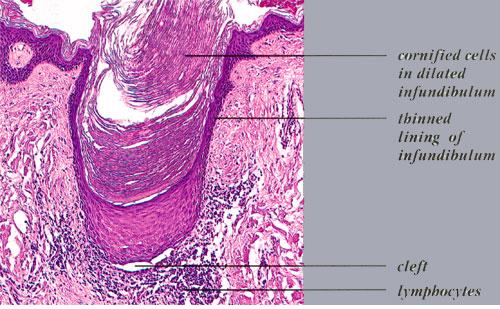

Alopecia of Lichen Planus =الحاصة بسبب الحزاز المنبسط